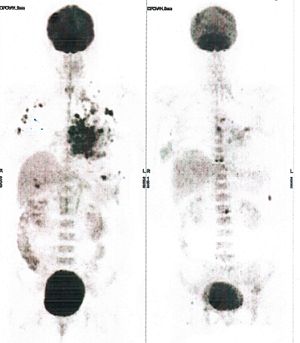

Below are some of the cases, from more than 80 cases we have treated so far with good results. When reading the PET/CT scans, the picture on the left is before treatment, and the picture on the right is after treatment. The intensity of black represents the activity of the cancer, but some black areas are not cancer: brain, heart, radioactive urine in bladder. For the heart, the intensity of black depends on the number of hours of fasting: if more than 10 hours, the heart is not even black, but if fasting is less than 6 hours, it is very black. The intensity of black in the brain can be variable in different scans depending on the brain activity at the time of the scan. The intensity of black in the radioactive urine can also be variable due to the hydration of patients and the time of injection of diuretic.

CASE NO: 9 (NHL + LUNG CANCER)

A middle-aged man successfully treated for non-Hodgkin’s lymphoma, came back with massive right lung and pleural cancer. After just 2 treatment, all the cancer went into remission. Treatment is continuing to prevent recurrence.

CASE NO: 10 (LUNG CANCER)

An old man with right lung cancer refused all cancer treatment, but was convinced to try our new cancer treatment because there is no severe side effect. After 3 treatment, the cancer shrunk to less than half the original size. He did not come back to continue the treatment.

CASE NO: 11 (NASOPHARYNGEAL CARCINOMA)

Old women successfully treatment for nasopharyngeal carcinoma, but two years later, she presented with massive liver and bone metastases while the cancer in the nasopharyngeal region did not recur. After a few treatment most of the cancer had regressed, and the remaining ones are less active. Treatment will continue until complete remission.

CASE NO: 12 (ENDOMETRIAL CANCER)

Old women previously treated for endometrial cancer came back with massive metastases in lymph nodes. After a few treatment almost all the cancer went into remission (the black area in the left abdomen is radioactive urine in the left kidney: arrow)